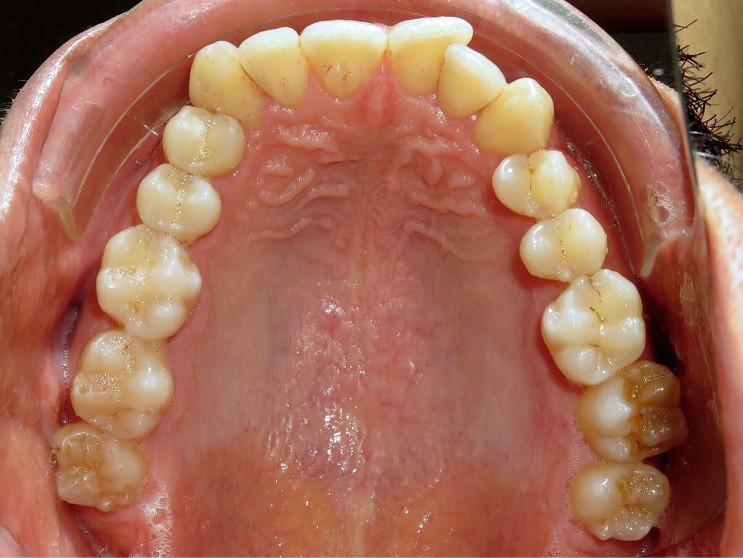

Une fois le sens transversal traité, la correction s’est portée sur le décalage sagittal de Classe II au niveau dentaire (fig. 3). La présence de tip forward sur les dents des secteurs latéraux maxillaires signifie que les apex de ces dents sont plus ou moins bien placés. Des mouvements de version sont suffisants. C’est pourquoi a été retenue la solution suivante :

- collage au maxillaire d’un segment d’arc acier 019 x 025 (traité au rhodium à des fins esthétiques) sur les canines et les premières molaires maxillaires avec du composite (contenu dans une carpule) destiné au collage des fils contention (choisi pour sa résistance et sa facilité de mise en œuvre) ;

- réalisation d’une gouttière mandibulaire rigide englobant l’ensemble des dents mandibulaires. Cette gouttière a pour but de relier l’ensemble des dents de l’arcade inférieure (ancrage) et d’obtenir une désocclusion.

- collage de boutons sur les 13 et 23 (en composite pour améliorer l’esthétique) et de boutons métalliques (pour le confort) sur les 36 46

- port d’élastiques (3/16 4,5 Oz) reliant les boutons maxillaires à ceux mandibulaires pour obtenir une force de recul sur l’arcade supérieure et d’avancée sur l’arcade opposée (les mouvements ont été facilités par les extractions des 18 28). Les prémolaires n’étant pas collées, le mouvement généré est un mouvement de version et donc de redressement (car tipées au départ). Il est à noter que les boutons canins sont collés le plus cervicalement possible pour avoir une traction oblique avec les élastiques inter-arcades, afin d’avoir un mouvement de descente des canines supérieures qui sont trop hautes. L’intérêt d’avoir une gouttière mandibulaire par rapport à un arc lingual ou un dispositif multi-attaches, c’est qu’une gouttière contrôle mieux les mouvements de vestibulo-version des incisives mandibulaires induits par les élastiques.